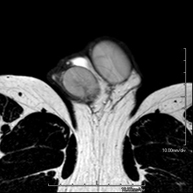

Prova diagnòstica no invasiva que consisteix en l'obtenció d'imatges d'alta definició anatòmica del sistema urinari mitjançant l'ús d'un camp electromagnètic i ones de ràdio (amb un emissor i un receptor). No utilitza radiació ionitzant. Cal utilitzar contrast paramagnètic (Gadolini) que s'expel·lirà a través del sistema urinari i ens permetrà obtenir imatges en 2D i 3D. - RM de Pròstata

Prova diagnòstica no invasiva que consisteix en l'obtenció d'imatges d'alta definició anatòmica de la glàndula prostàtica mitjançant l'ús d'un camp electromagnètic i ones de ràdio (amb un emissor i un receptor). No utilitza radiació ionitzant. S'utilitza una bobina endorectal per obtenir imatges de màxima definició anatòmica de la pròstata i permetre fer l'estudi espectroscòpic (estudi a nivell molecular que ajuda a diferenciar les cèl·lules d'origen maligne o tumoral). També es realitza l'estudi amb contrast paramagnètic, que aporta una millor definició tissular. Aquesta prova dura uns 40 minuts, durant els quals el pacient haurà d'estar el més quiet possible. Requereix una neteja del còlon com a preparació prèvia. Aquesta prova està especialment indicada en aquells pacients amb sospita de neoplàsia de pròstata, amb neoplàsia de pròstata coneguda per l'estadiatge tumoral, per a l'estudi de localització del tumor prostàtic com a guia o mapa per a la biòpsia, per al seguiment dels pacients amb neoplàsia de pròstata tractats amb tractament quirúrgic o radioteràpic, davant d'una sospita de reincidència de la neoplàsia de pròstata, etc. - RM de Cos sencer (Total body)